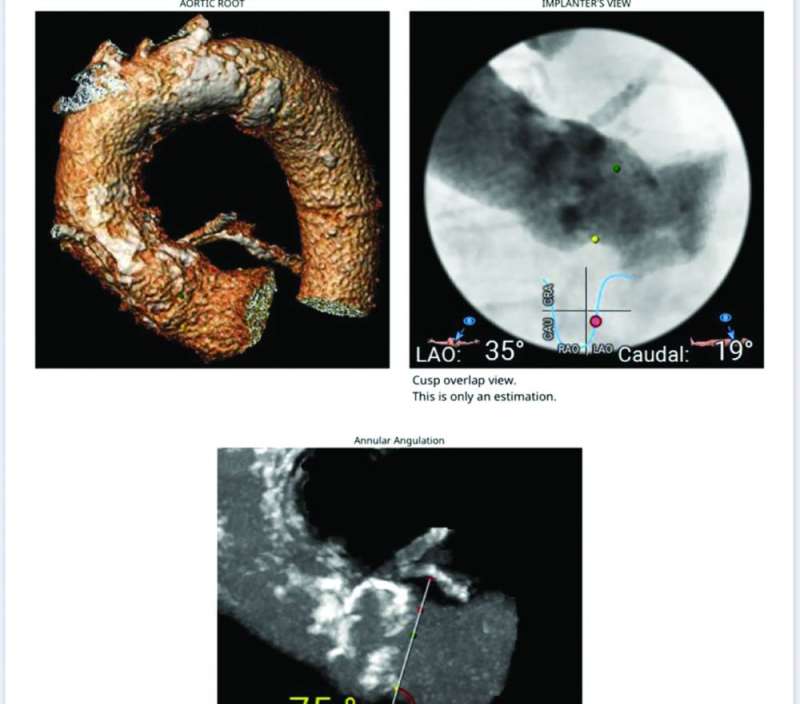

وأضاف «ساعدت التقنية الجديدة في الصمام، بوجود طبقة تساعد على ثباته بوضعه المحدد بدقة في هذه المسافة الضئيلة،على نجاح عمل تبديل الصمام. وقد تمت الاستعانه بسونار القلب عن طريق المريء وتقنية الإيكو ثلاثي الأبعاد (3D TOE) لتثبيت ووضع الصمام بدقة شديدة من دون التداخل مع شرفات الصمام الميترالي المعدني. وتعد هذه الحالة الأولى من نوعها في الشرق الأوسط، من الحالات النادرة عالمياً، التي يتم فيها تبديل الصمام الأورطي عن طريق القسطرة بوجود صمام ميترالي معدني باستخدام مثل هذه التقنيات الحديثة».

من جانبه، قال الدكتور طه لـ «الراي»، إنه «في حالة ثانية ساعدت نفس التقنية الحديثة باستخدام الصمام الجديد في تبديل صمام اورطي، ووضعه بدقة شديدة لمريض في العقد الثامن بوجود شريان أورطي مستعرض (Horizontal Aorta) بزواية إنزال تصل إلى 80 درجة، مما يسبب صعوبة شديدة في وضع الصمام بدقة في مثل هذه الحالات النادرة».